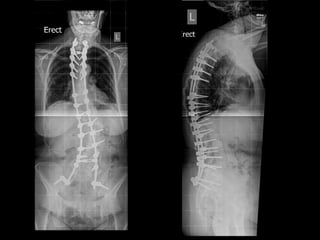

FUSION FOR LOWBACK PAIN Noninstrumented fusion

FUSION FOR LOWBACK PAIN Interbody fusion

remove the disc Interbody fusion • removethe pain source • stop the movement FUSION FOR LOW BACK PAIN